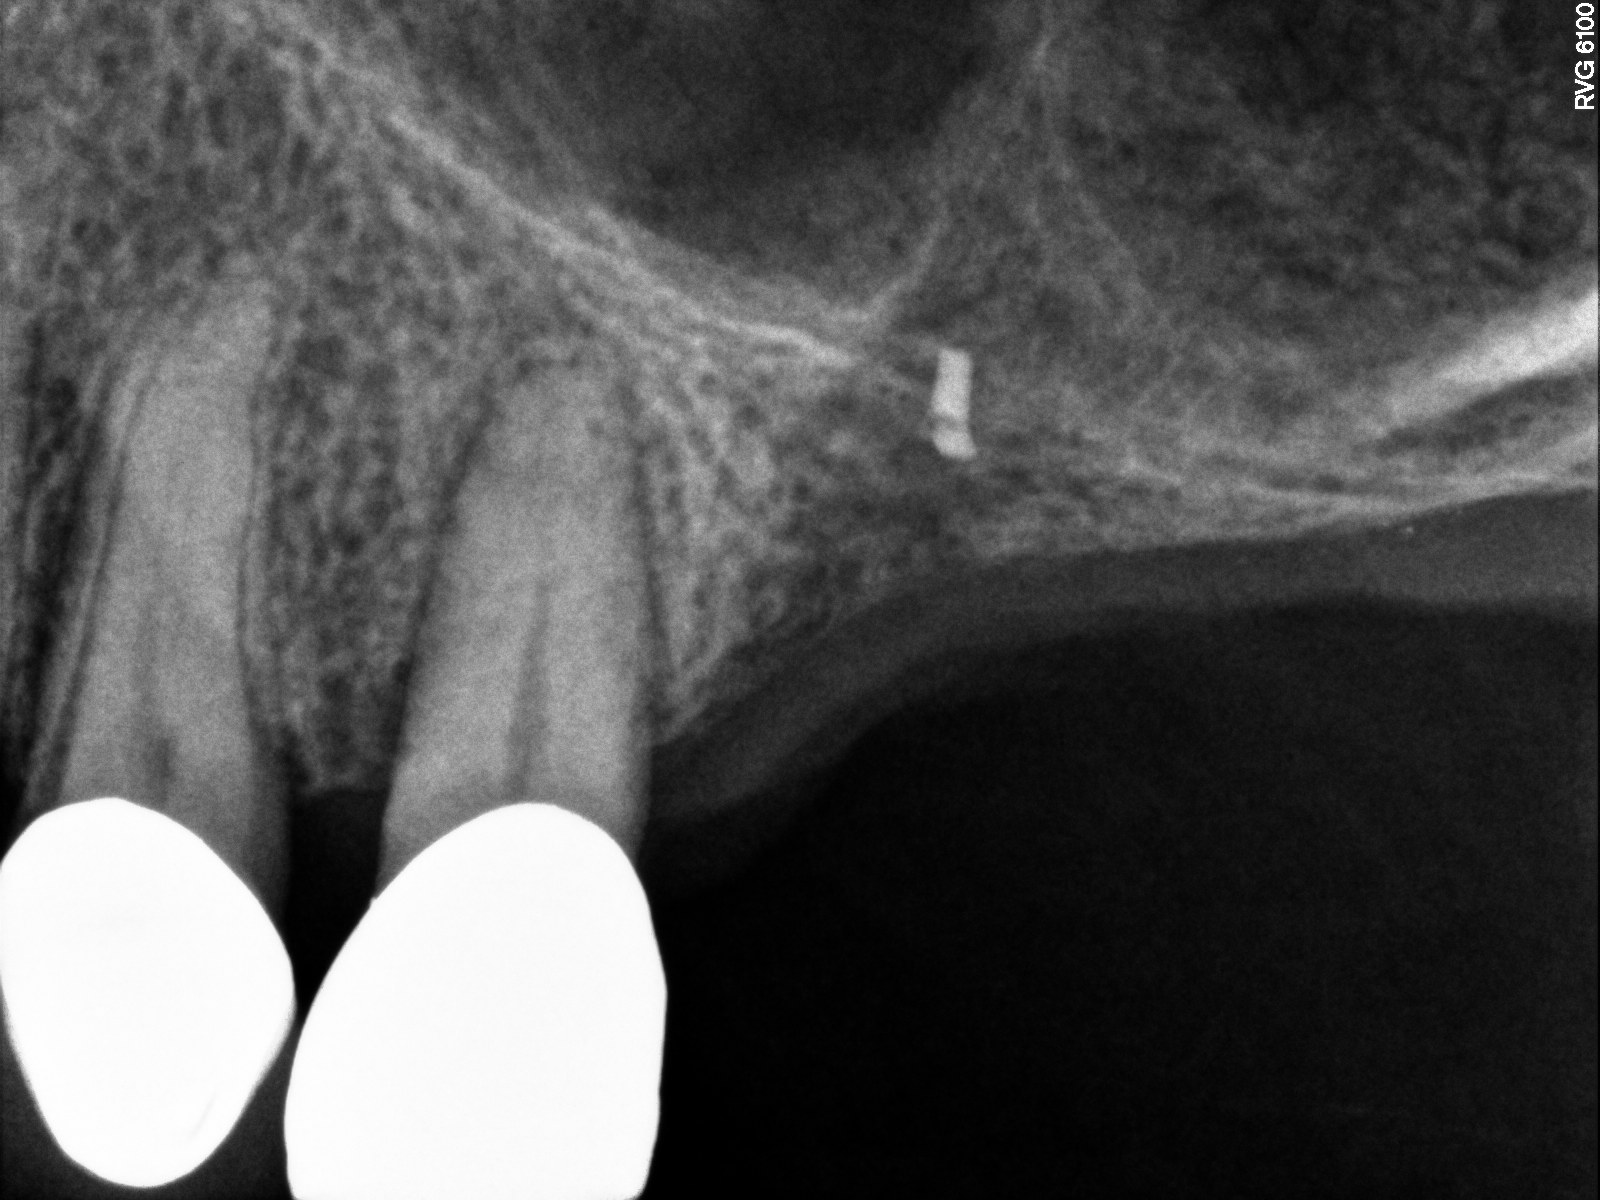

Case 3. Preoperative radiograph showing about 3.5 mm of ridge height.

Fig. 20